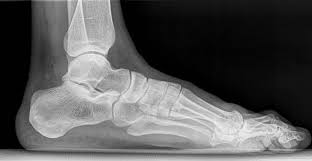

Essa subespecialidade trata entorses, fraturas, esporão de calcâneo, fascite plantar, joanetes (hálux valgo), deformidades nos dedos, lesões nos tendões e instabilidades crônicas do tornozelo. Também cuida de dores causadas por má pisada, uso de calçados inadequados e alterações estruturais dos pés.

Com um diagnóstico preciso e tratamento adequado — que pode envolver palmilhas personalizadas, fisioterapia ou cirurgia é possível aliviar a dor e melhorar significativamente a qualidade de vida do paciente.

Esporão de calcâneo: Crescimento ósseo anormal no calcanhar, associado frequentemente a dores no pé.